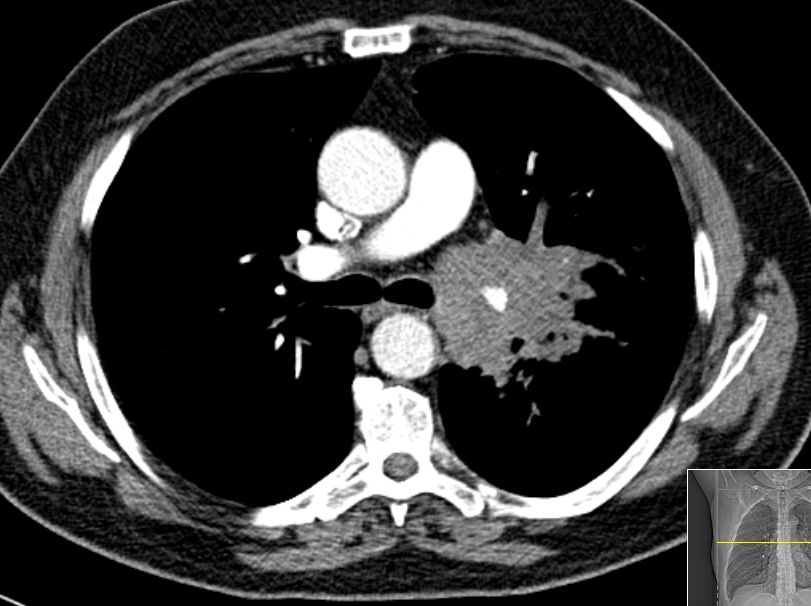

65-jähriger Mann mit einem SCLC rechts zentral, G3,Ki67 90%, chromogranin – negativ, CD56 negativ, CD45 negativ, Pankeratin z.T. positiv.![]() |

![]() |

![]() | ||